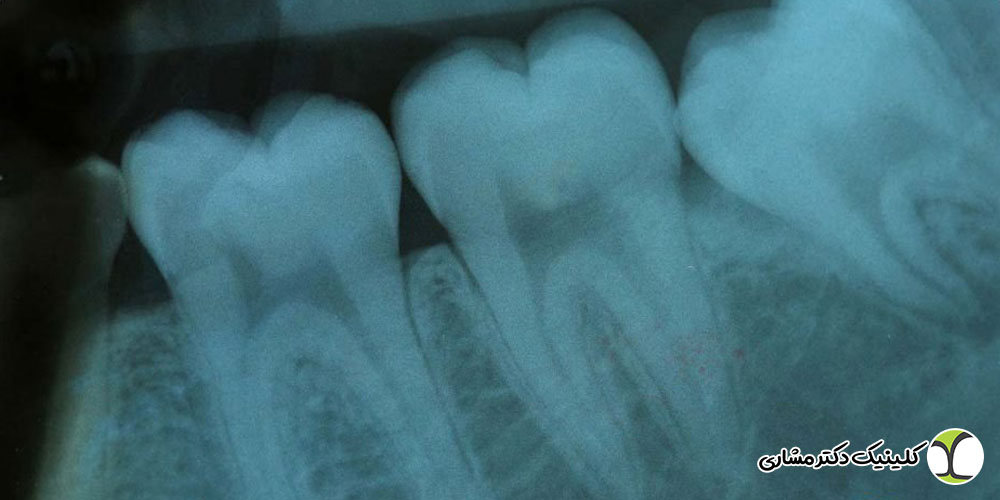

رادیوگرافی دندان، به ویژه رادیوگرافی پریآپیکال، امکان مشاهده تغییرات ساختاری در نواحی اطراف ریشه را فراهم میکند. این تغییرات اغلب پیش از آنکه بیمار درد یا علائم واضح داشته باشد، در تصویر ظاهر میشوند.

از طریق رادیوگرافی میتوان موارد زیر را بررسی کرد:

- تیره شدن ناحیه اطراف ریشه که نشاندهنده تحلیل استخوان یا التهاب است

- از بین رفتن لامینا دورا، لایه نازک استخوانی اطراف ریشه

- تحلیل استخوان اطراف آپکس ریشه

- تغییر شکل یا طول ریشه در اثر التهاب شدید

- مشاهده مسیرهای تخلیه چرک یا سینوس تراکت

این نوع عفونت در نوک ریشه ایجاد میشود و شایعترین نوع عفونت ریشه است. در رادیوگرافی پریآپیکال، عفونت به صورت یک هاله تیره اطراف آپکس دیده میشود که نشاندهنده تحلیل استخوان و التهاب است.

بررسی پریآپیکال: دندانپزشک ابتدا وضعیت نوک ریشه را بررسی میکند تا هرگونه تغییر در تراکم استخوان یا هاله تیره مشخص شود.

ارزیابی لامینا دورا و تراکم استخوان اطراف ریشه: تحلیل لامینا دورا و تراکم استخوان به تشخیص میزان پیشرفت عفونت و شدت التهاب کمک میکند.

مقایسه با دندانهای سالم: با مقایسه ریشه دندان سالم و دندان مشکوک، تغییرات جزئی که ممکن است در مراحل اولیه عفونت رخ داده باشد، مشخص میشود.

بررسی خطوط شکستگی ریشه: در برخی موارد، شکستگیهای طولی یا میکرودرجهای ریشه باعث نفوذ باکتریها و عفونت میشوند. رادیوگرافی کمک میکند این شکستگیها شناسایی شوند.

تعیین میزان گسترش عفونت: با بررسی نواحی اطراف ریشه، دندانپزشک میتواند تشخیص دهد که آیا عفونت محدود به یک دندان است یا به استخوان و دندانهای مجاور نیز سرایت کرده است.